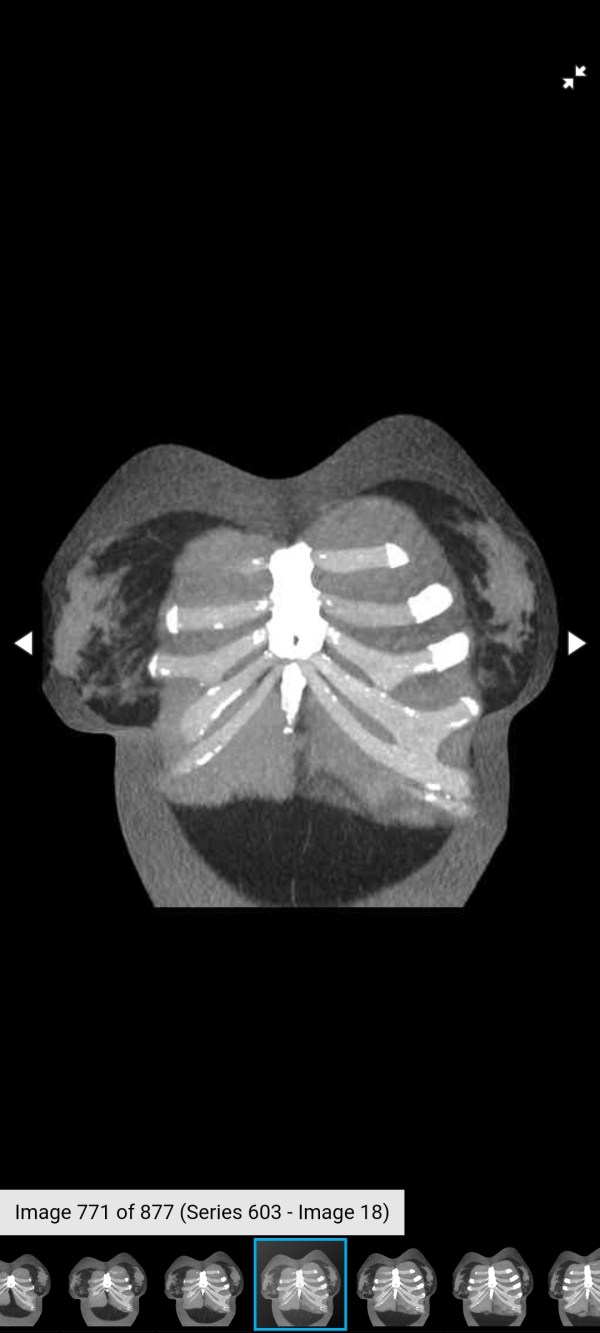

Slipping Rib Syndrome & Bridging Cartilage Fracture

Had to get another CT scan of my ribs for Dr. H. The cover photo for this post is an older CT scan - but you get the idea. I'm about 8 months post-op from my last Slipping Rib Syndrome surgery and I've already had my follow-up with Dr. Hansen a few weeks ago. We... Continue Reading →